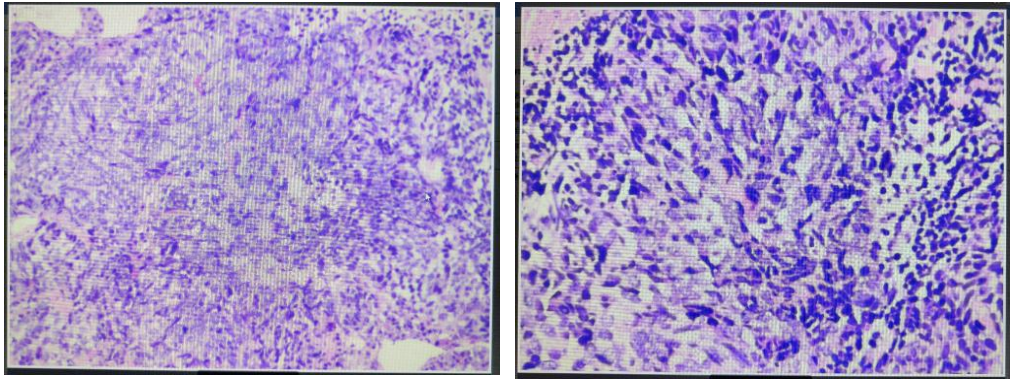

2022年5月10日行超声引导下右肺肿块穿刺活检,病理诊断:(右肺)小细胞癌。

免疫组化结果:CD56(+),Ki67(60%+),CgA(+),TTF-1(+),Syn(+),P40(-),Napsin-A(-),CD5/6(-),CK(Pan)(+),LCA(-)。